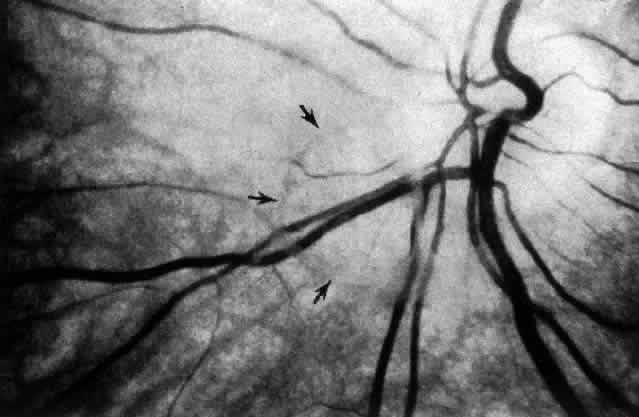

The posterior vitreous cortex is 100-110 μm thick50,60 and, as shown in Figure 12, consists of densely packed collagen fibrils.50,60,152 There is no vitreous cortex over the optic disc (see Figs. 4A AND 13), AND the cortex is thin over the macula due to rarefaction of the collagen fibrils.50 The prepapillary hole in the vitreous cortex can sometimes be visualized clinically when the posterior vitreous is detached from the retina (Fig. 14). If peripapillary glial tissue is torn away during PVD and remains attached to the vitreous cortex about the prepapillary hole it is referred to as Vogt's or Weiss's ring. Vitreous can extrude through the prepapillary hole in the vitreous cortex (see Fig. 4A) but does so to a much lesser extent than through the premacular vitreous cortex (see Figs. 4B AND D and 13). Jaffe153 has described how vitreous can extrude into the retrocortical space created after PVD and has proposed that persistent attachment to the macula (Fig. 15) can produce traction and certain forms of maculopathy.154,155 Although there are no direct connections between the posterior vitreous and the retina, the posterior vitreous cortex is adherent to the internal limiting lamina of the retina, which is actually the basal lamina of retinal Müller cells. The exact nature of the adhesion between the posterior vitreous cortex and the internal limiting lamina is not known but probably results from the presence of various extracellular matrix molecules.91 This concept is supported by studies156,157 in which vitreous cortex separation from the retina was induced using agents that acted on extracellular matrix components that could bind the posterior vitreous cortex to the internal limiting lamina of the retina.

Fig. 14. The posterior vitreous is detached, and the prepapillary hole in the posterior vitreous cortex (arrows) can be seen anterior to the optic disc (slightly below and to the left of the optic disc) (Sebag J: The Vitreous--Structure, Function and Pathobiology. New York, Springer-Verlag, 1989)